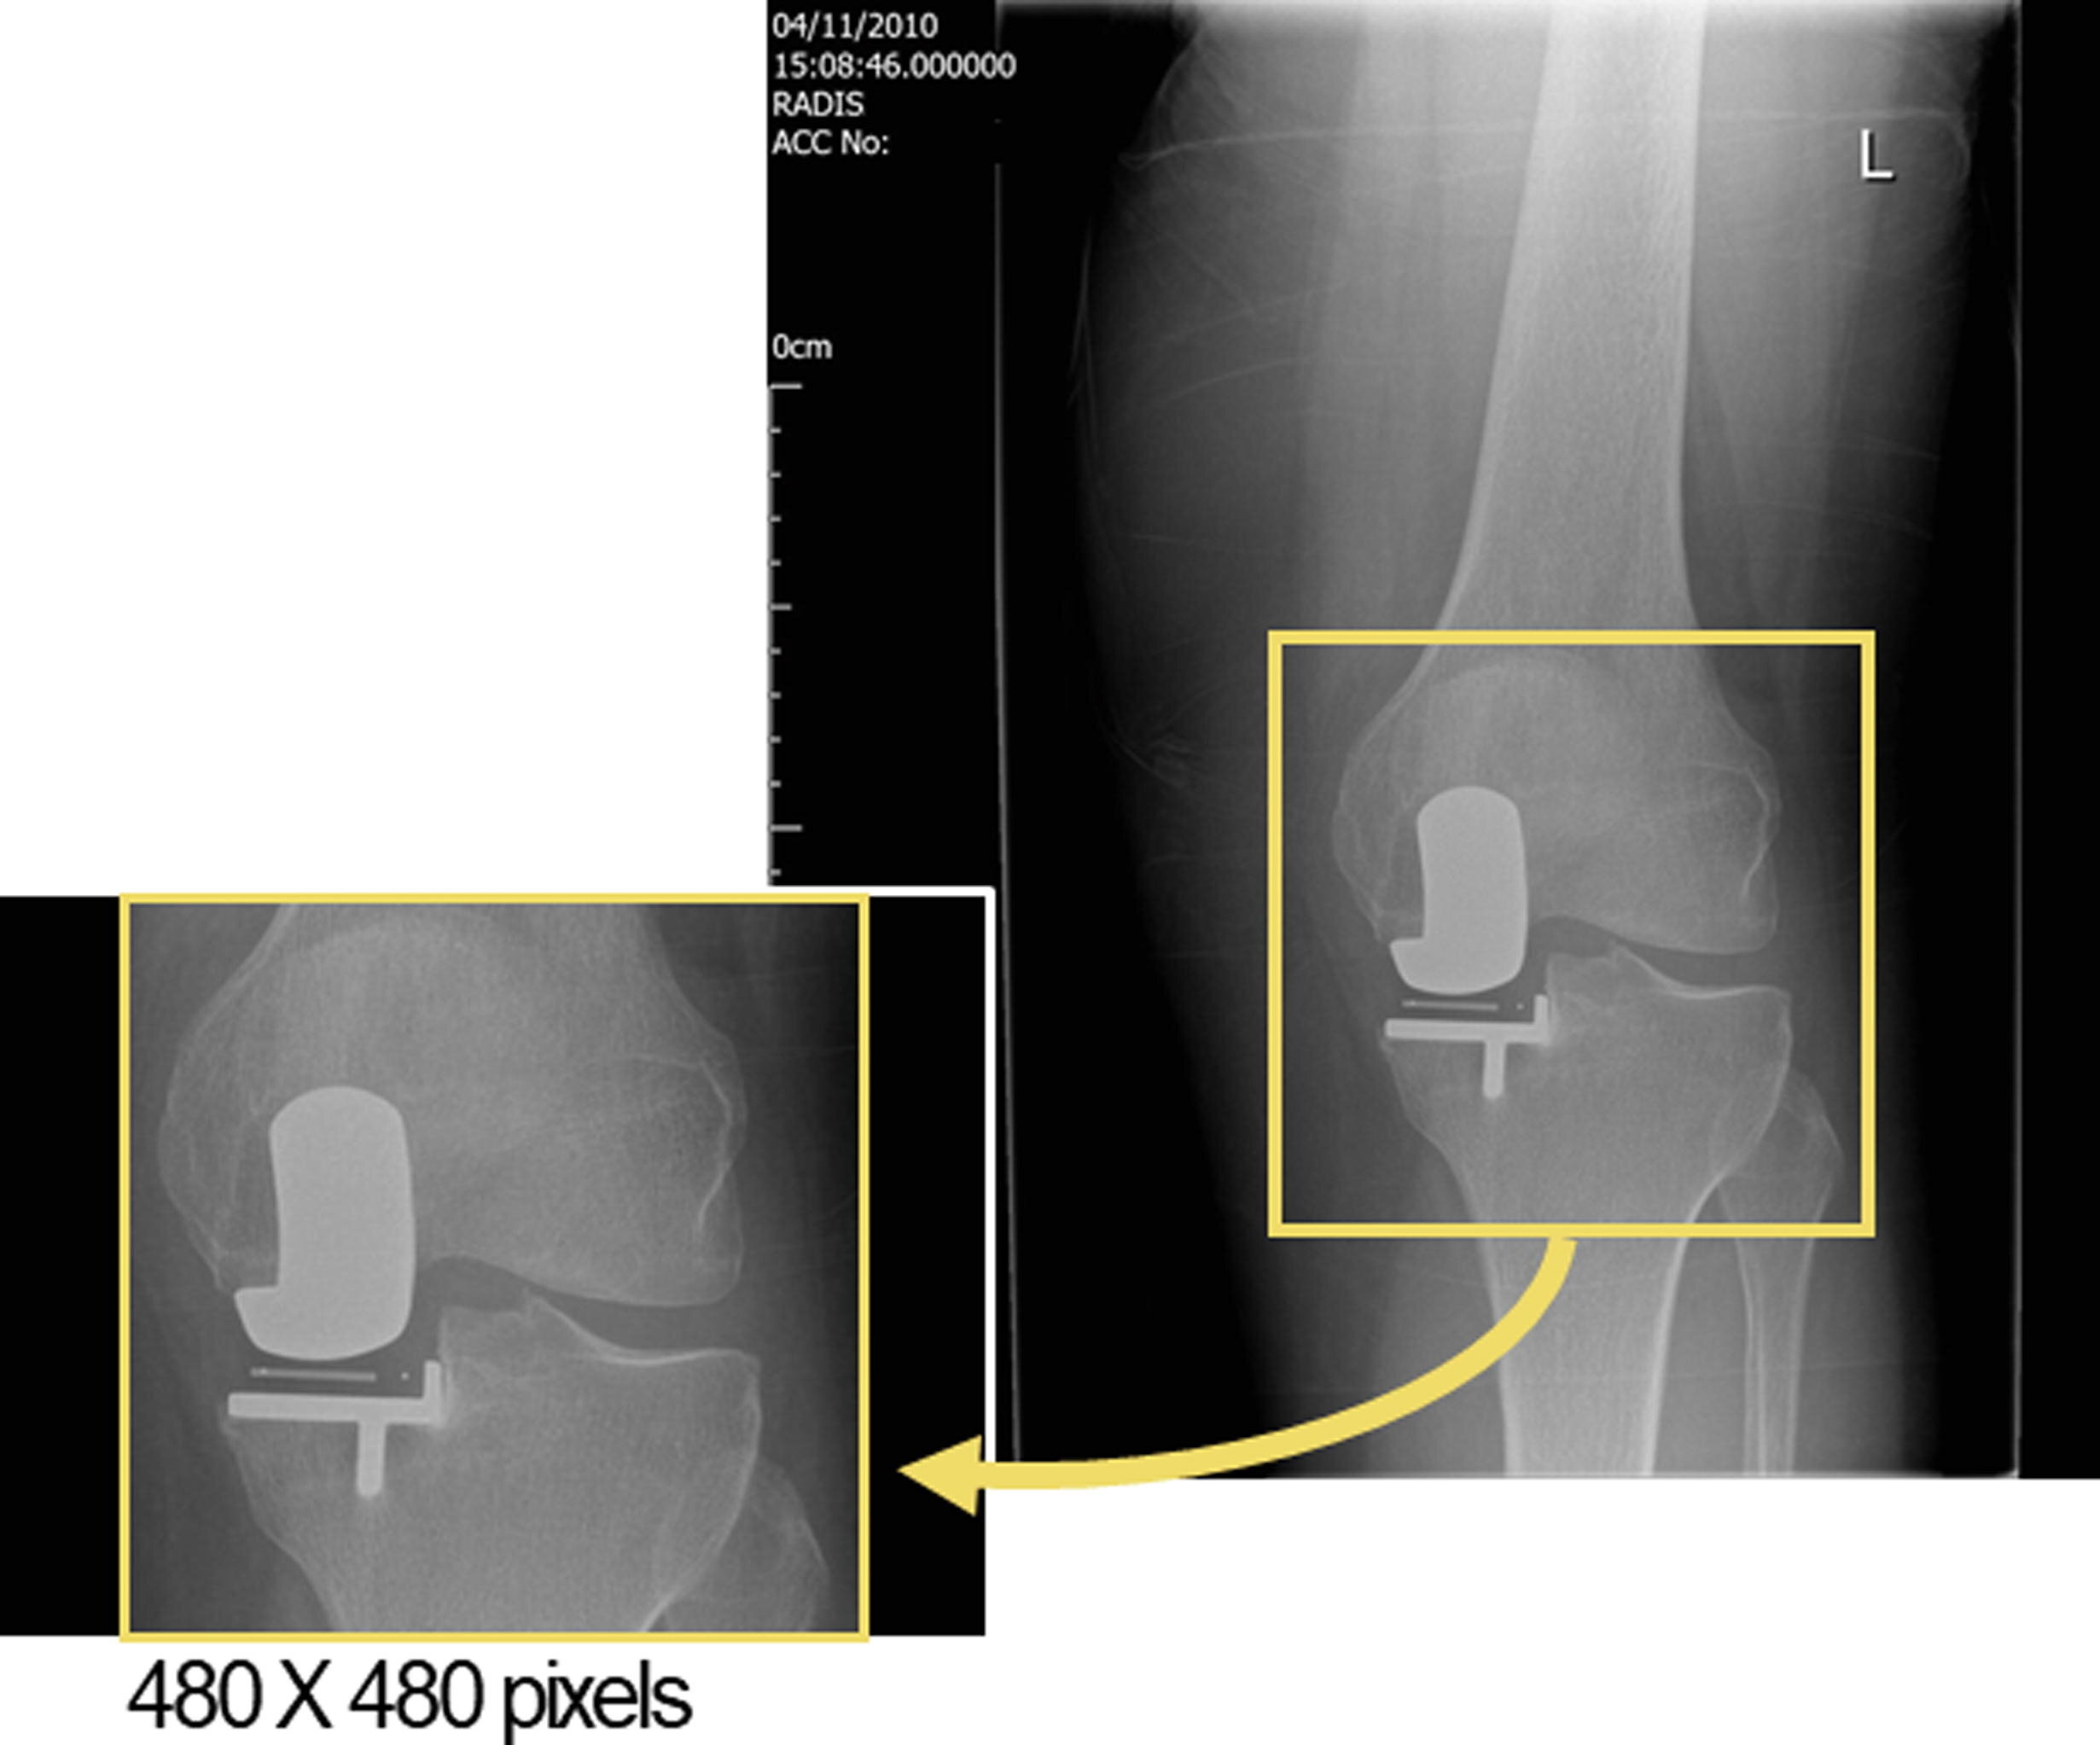

Исследование, проведенное в NDORMS и опубликованное в журнале The Knee, показало, что ИИ может выявить паттерны, которые обычно незаметны для врачей. В рамках эксперимента специалисты обучили модель машинного обучения анализировать рентгеновские снимки, чтобы предсказать, у кого из пациентов будет плохой исход после операции.

Команда проанализировала более 900 рентгенов, сделанных через год после операции, и сравнила прогнозы хирургов с результатами ИИ. Модель машинного обучения предсказала плохие результаты в 71% случаев, в то время как хирурги смогли правильно определить их только в 0−7% случаев.